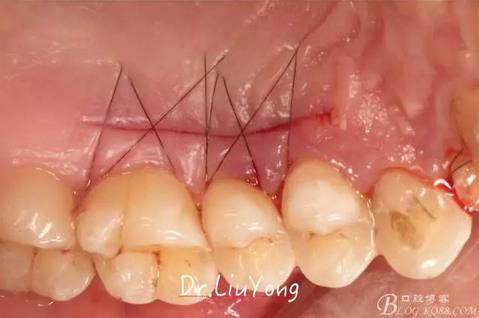

將結(jié)締組織瓣縫合固定于受區(qū),如上圖

縫合關(guān)閉供瓣區(qū)域,如上圖